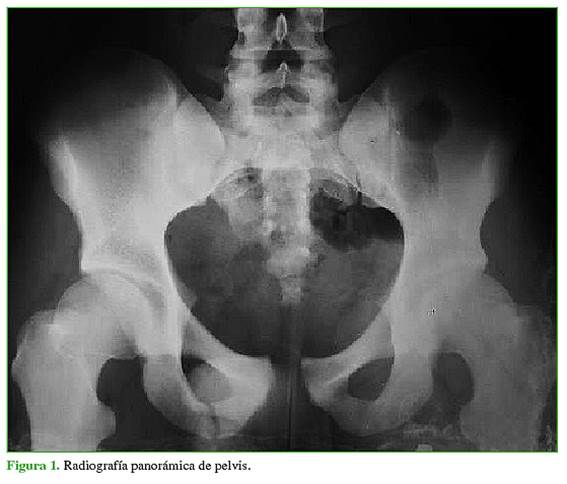

Las fracturas se clasificaron, según la clasificación de Young y Burgess, en las radiografías panorámica (Figura 1), de entrada (Figura 2) y de salida de pelvis (Figura 3), y tomografía computadorizada.

Introducción: Las fracturas de pelvis se asocian frecuentemente a un trauma de alta energía. La tasa de mortalidad varía del 5% al 46%. El objetivo de este estudio fue explorar si las variables analizadas se asociaron con el resultado final del tratamiento de las fracturas de pelvis APCII (AO/OTA: 61B2.3). Materiales y Métodos: Se evaluó a 23 de 79 pacientes luego de aplicarles los criterios de selección. Las fracturas fueron clasificadas, según Young y Burgess, en una radiografía panorámica de pelvis, de entrada y de salida, y tomografía computarizada. Se evaluó el resultado clínico según la escala funcional de Majeed. Las variables evaluadas fueron: tratamiento en la urgencia, lesiones asociadas, días de espera hasta la cirugía, fijación utilizada, reducción posquirúrgica inmediata, infección del sitio quirúrgico. Resultados: No se halló una diferencia estadísticamente significativa entre el tipo de tratamiento realizado en la urgencia, las lesiones asociadas, los días de espera hasta la cirugía y el tipo de fijación, con el resultado final a largo plazo. Los pacientes que tuvieron una reducción posoperatoria inmediata <1 cm y los que no sufrieron una infección del sitio quirúrgico obtuvieron mejores resultados funcionales, de manera estadísticamente significativa. Conclusión: Las variables calidad de la reducción posquirúrgica inmediata e infección del sitio quirúrgico en pacientes con fractura de pelvis APCII se asocian directamente con los resultados funcional y clínico a largo plazo.